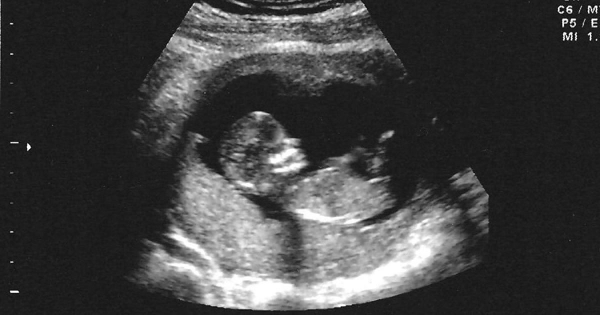

而當超音波探頭一放下去後,發現嬰兒已經14週了,「和平常不同的是,『恭喜』兩個字我實在說不出口。」